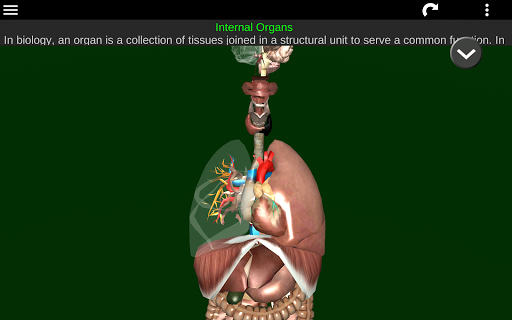

Internal Organs in 3D Anatomy لـ Vodafone Smart N9 Lite

(الأجهزة الداخلية في)

Internal Organs 3D Anatomy 3.4

Internal Organs 3D Anatomy 3.1

Organs 3D Anatomy 2.0.12

يمكنك هنا تنزيل ملف حزمة تطبيق أندرويد "Internal Organs 3D Anatomy" الخاصة بجهازVodafone Smart N9 Lite مجانًا، نسخة ملف حزمة تطبيق أندرويد - 3.4 للتحميل على Vodafone Smart N9 Lite اضغط ببساطة على هذا الزر. إنه سهل وآمن. نحن نقدم فقط ملفات حزمة تطبيق أندرويد الأصلية. إذا انتهكت أية مواد موجودة في الموقع حقوقك قم بإبلاغنا من خلال